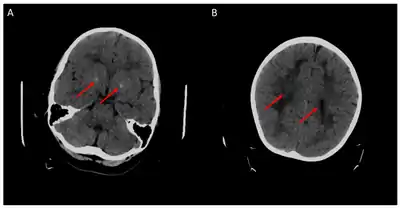

Figures